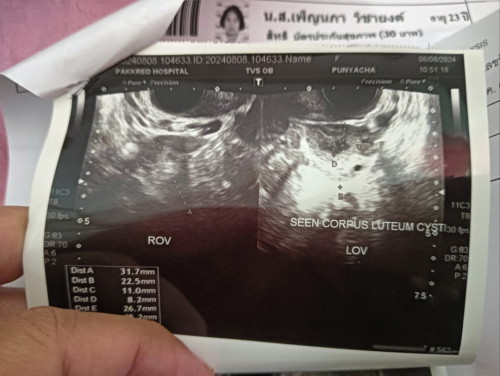

ตอนไปฝากครรภ์อายุครรภ์เก้าสัปดาห์ อัลตราซาวด์ผ่านหน้าท้องแล้วไม่เจอการเต้นของหัวใจ คุณหมอเลยอัลตราซาวด์ผ่านช่องคลอด จึงเห็นหัวสองหัวแต่ว่าตัวติดกัน แล้วน้องก็หยุดการเจริญเติบโตตั้งแต่ห้าสัปดาห์แล้ว ซึ่งเป็นปกติเพราะว่าน้องอยู่ในถุงตั้งครรภ์เดียวกัน คุณหมอบอกไม่เจอ เคสแบบนี้นานแล้ว คุณหมอต้องติดตามอาการและนัดขูดมดลูกวันที่ 15 ที่จะถึงนี้ ต้องติดตามอาการบ่อยบ่อยเพราะว่ามีประวัติการแท้งมาแล้วถึงสองครั้ง และครั้งนี้ที่สาม #แฝดสาม #แท้ง3